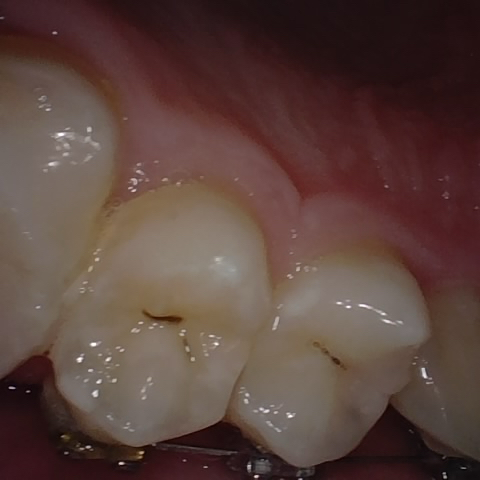

NHD39990

Annotated as "Good"

Original Image Rendering Image